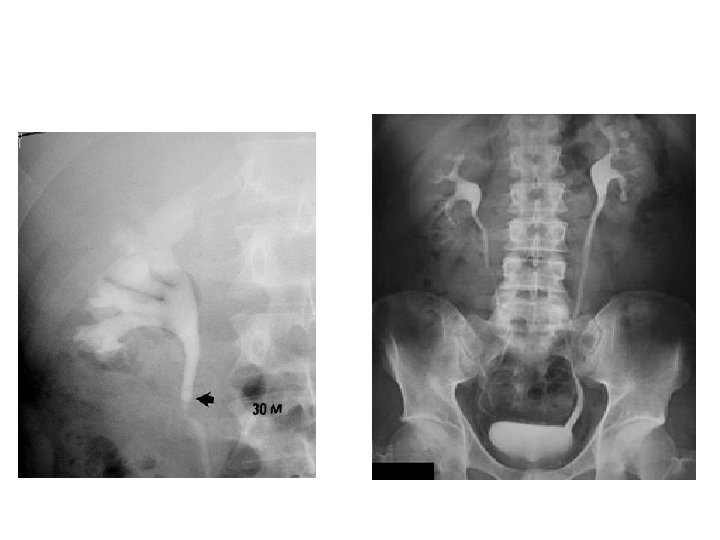

Radyolojik İnceleme • • • Direkt Üriner Sistem Grafisi Ultrasonografi İntravenöz Piyelografi Bilgisayarlı Tomografi Böbrek Sintigrafisi